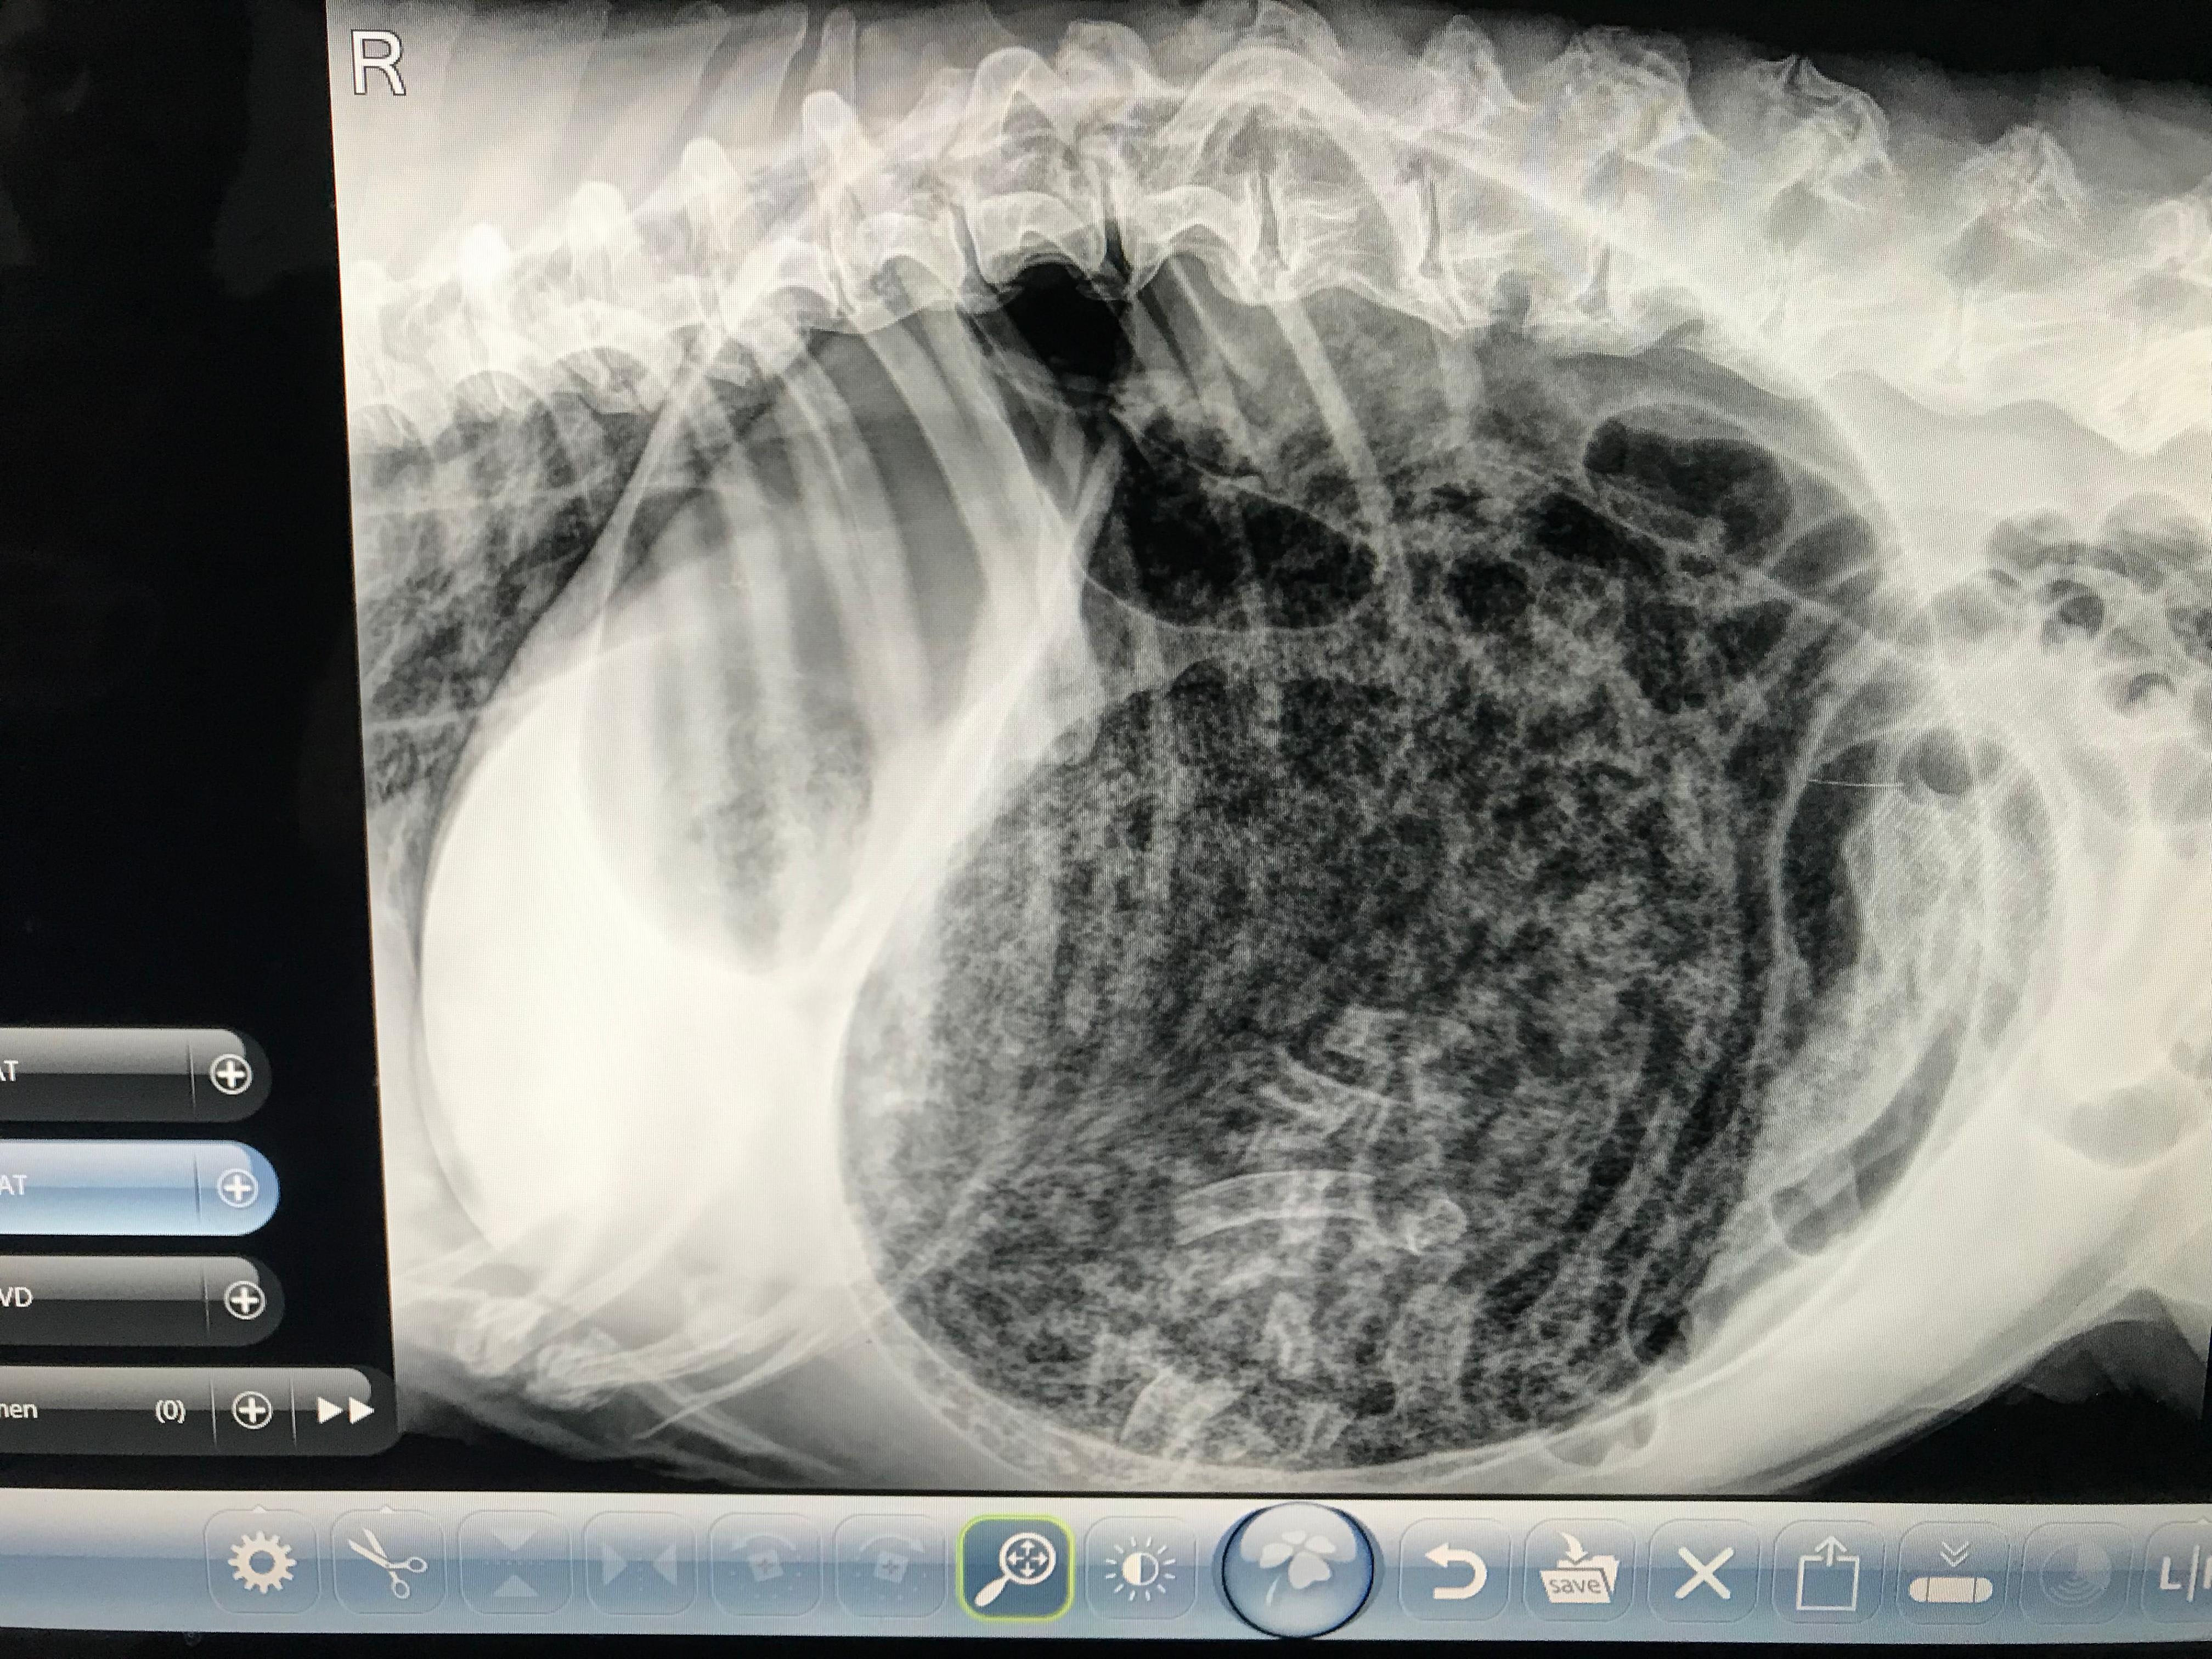

Hello, recently had a question answered regarding my dog being diagnosed with GDV, please can you confirm if in the X-ray attached in photos if the stomach did infact turn? She was heaving heavily and I could see her stomach had swollen significantly, she was also pacing around the house and refused to eat (did drink a lot of water at first), she did however not vomit at all. Thanks and kind regards

Thanks for using Petco Pet Education Center, formerly Petcoach! An official diagnosis requires at least 2 view radiographs. However, this 1 view definitely looks consistent with a GDV and warrants a veterinary evaluation as soon as possible. Best of luck!